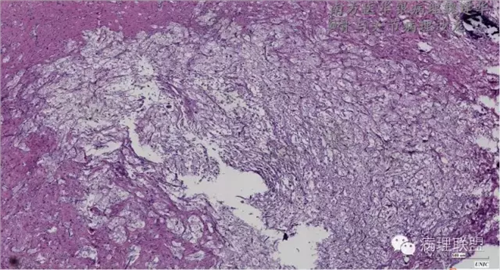

来源于组织细胞的相似性骨病ECD vs RDD 看图说话